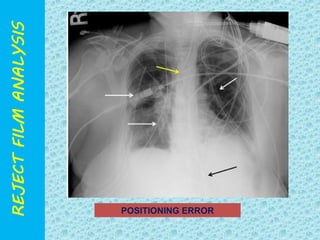

POSITIONING ERROR